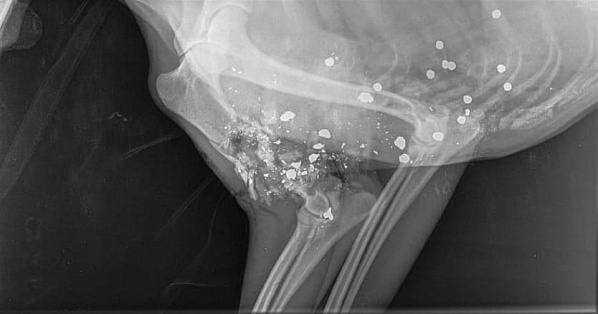

Нетрезвые местные жители решили поохотиться на территории приюта для собак «Дядя Феникс». Одно животное погибло, еще несколько ранены.

В тот момент, когда в приют приехали трое пьяных мужчин, собак охранял один лишь дежурный сотрудник — помешать расправе над животными он не смог. Как рассказал руководитель учреждения, видеокамера зафиксировала, как мужчины стреляют по животным из огнестрельного оружия.

Спустя полчаса к приюту подъехали другие сотрудники и участковый: трупа погибшей собаки не нашли — нападавшие зачем-то забрали его с собой. Они уже опознаны: это оказались жители станицы Грушевской, около которой и расположен временный питомник для собак. Чем животные помешали станичникам, теперь выясняют сотрудники полиции, сообщает «Аксай-город».